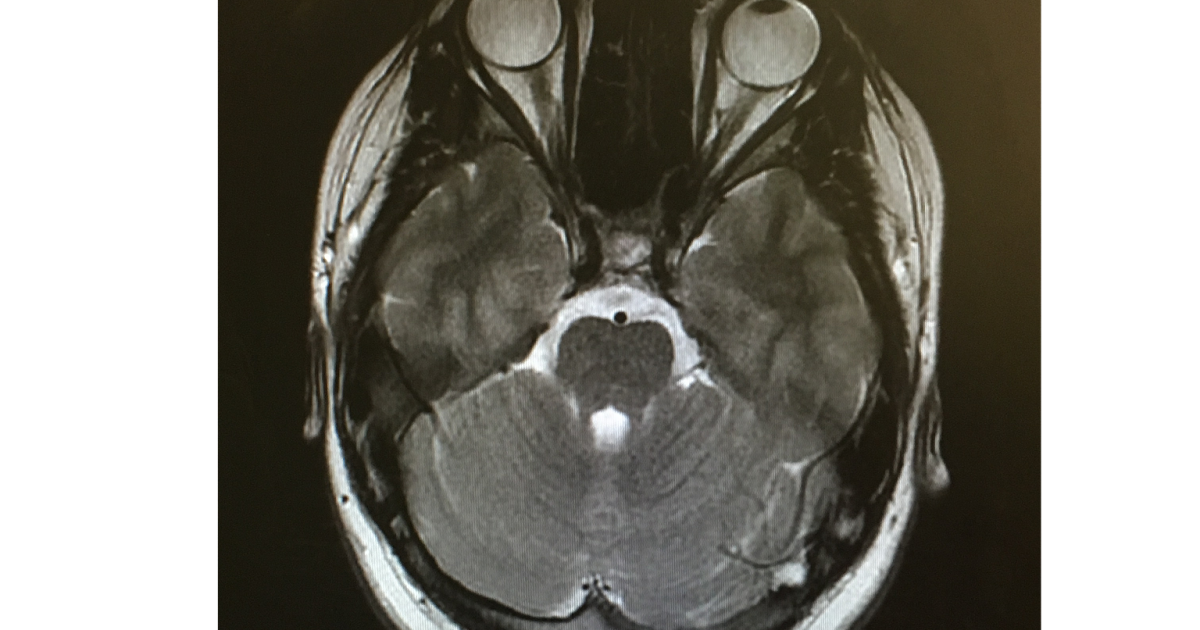

From myjourneywithcushingsdisease.blogspot.com

Fixing The Fat Girl's Future My Journey with Cushing's Disease MRI Cushing's Disease Mri — the sensitivity of mr imaging in cushing disease is not known nor is the prognostic significance of “mr. The sensitivity of mr imaging in cushing disease is not known. — ct or mri scans can take pictures of the pituitary and adrenal glands to see if anything shows up, such as tumors. 2 mr imaging of the.. Cushing's Disease Mri.